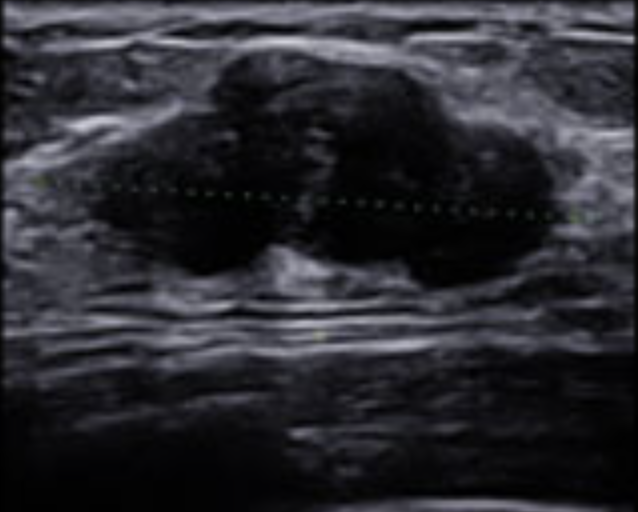

유방 섬유선종 크기, 초음파 사진

유방 섬유선종의 진단과 검사는 일반적인 진찰만으로도 진단이 가능하나 그 확률이 20~50%로 부정확할 만큼 낮아 유방 촬영, 유방 초음파를 같이 시행하여 진단합니다.

유방 섬유선종이라면 유방 촬영상 경계가 잘 보이고 둥근 결절이 보이며 내부에 석회화를 보이기도 합니다.